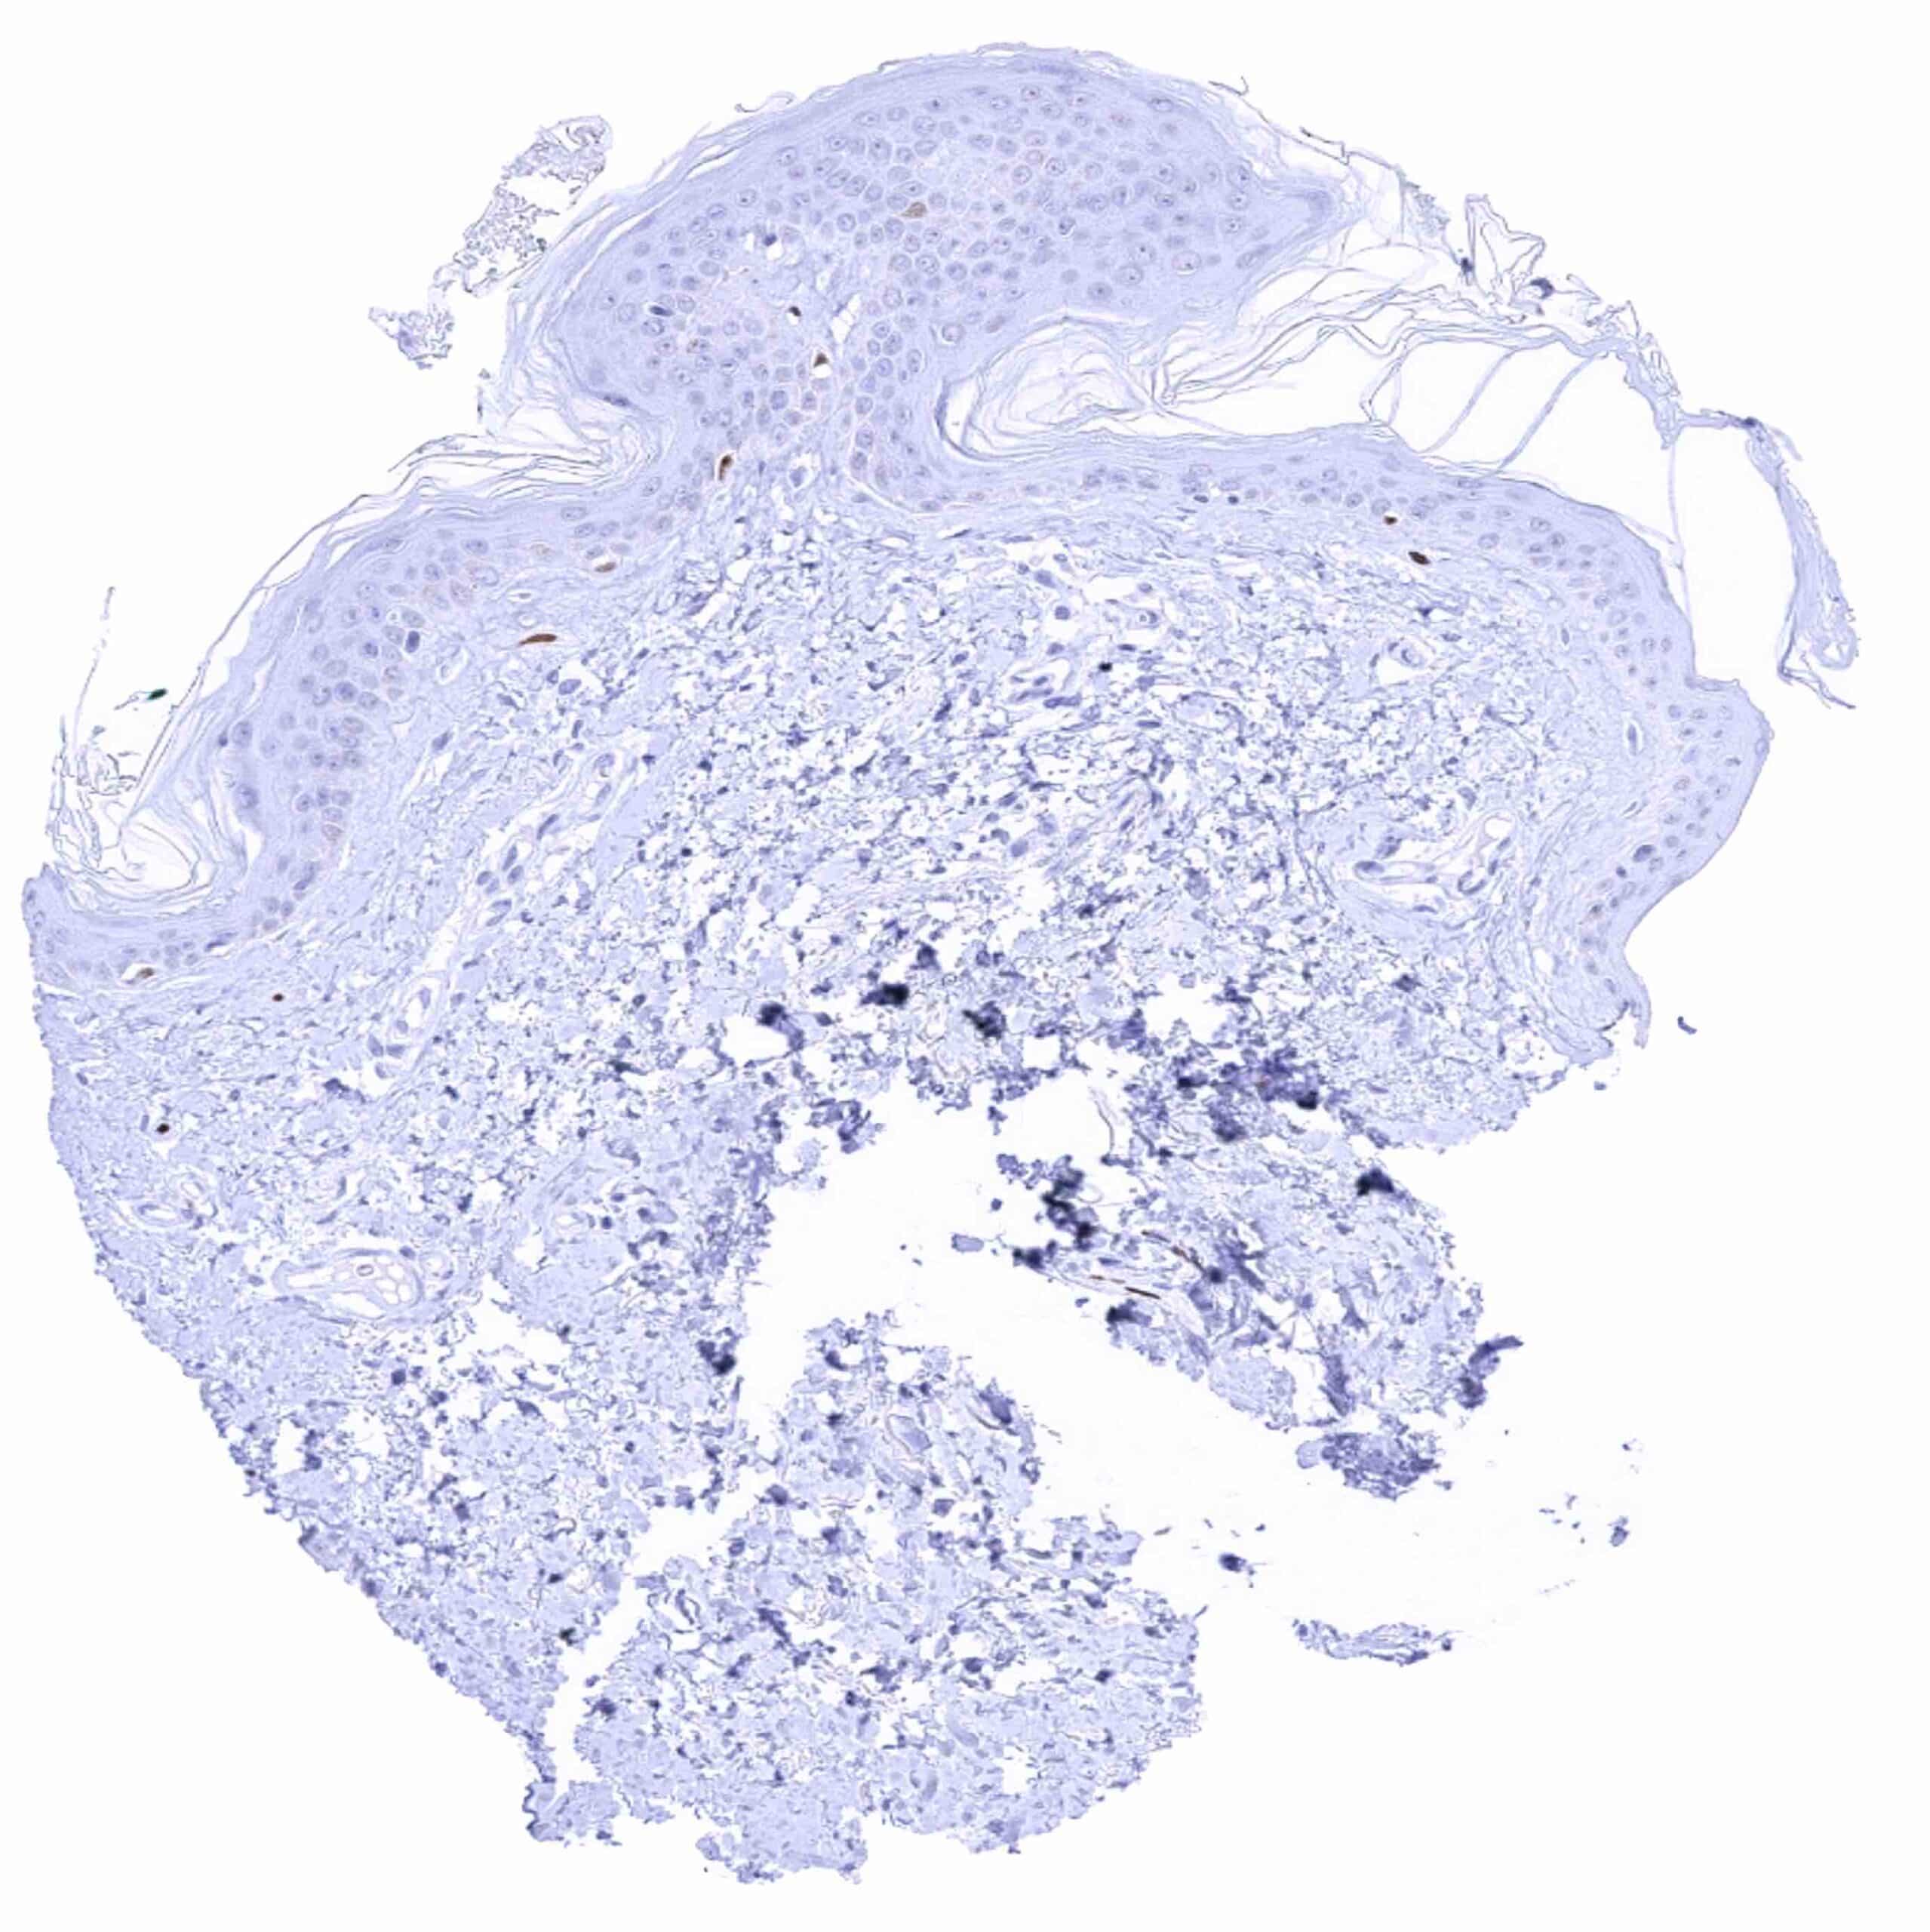

Skin – Strong SOX2 positivity few epidermis-adjacent spindle shaped (neural_) cells in the dermis.jpeg